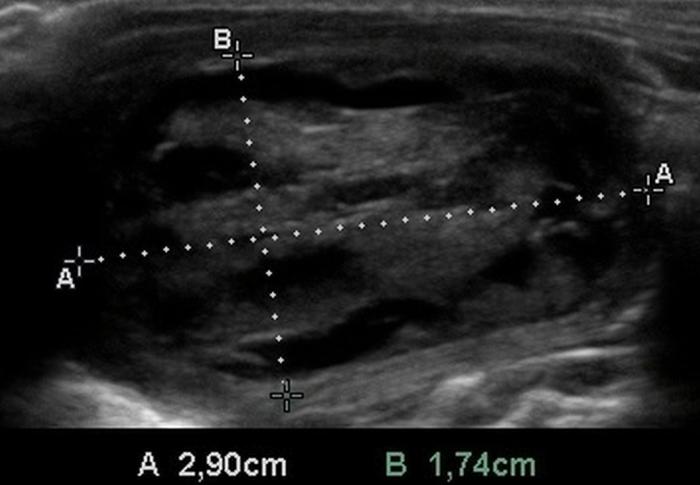

El uso de estructuras vasculares adyacentes como referencias anatómicas ha sido una estrategia útil en ecografía veterinaria para estandarizar las mediciones de órganos pequeños como la glándula tiroides. En este contexto, Bandula Kumara et al. (2019) propusieron la medición de la relación entre el diámetro tiroideo (TD) y el diámetro de la arteria carótida común (CCA) como una forma práctica de evaluar el tamaño de la glándula en perros clínicamente normales (Figura 5A-B).

Los autores realizaron un estudio en el que midieron el diámetro anteroposterior de los lóbulos tiroideos y el diámetro externo de la CCA en cortes transversales obtenidos a nivel del cuello medio. Encontraron que esta relación se mantiene relativamente constante entre razas y tamaños corporales, sugiriendo que puede ser utilizada como parámetro de referencia ecográfica. Específicamente, en perros adultos sanos, la relación TD/CCA fue de 1.74 ± 0.40 (rango 1.11–2.43)6. Si los valores se encuentran por debajo del rango normal pueden ser considerados potencialmente indicativos de hipoplasia tiroidea o atrofia glandular.

Una ventaja de esta relación es que la arteria carótida común es fácilmente identificable ecográficamente, presenta un diámetro estable y poco variable en condiciones fisiológicas, y se ubica en estrecha proximidad con la glándula tiroides. Esto la convierte en una excelente estructura de referencia para normalizar mediciones entre individuos de diferente tamaño corporal, permitiendo evaluaciones objetivas en poblaciones mixtas de perros de compañía.